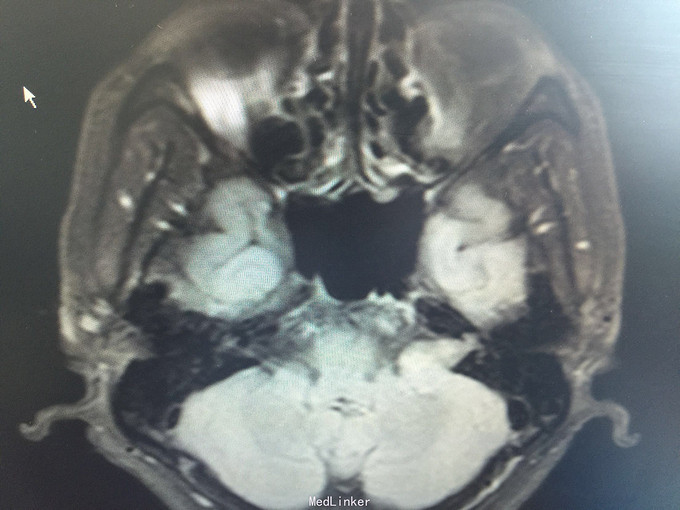

男,52岁,以“左耳鸣、听力下降1年余”入院。 现病史:1年余前看电视时出现左耳鸣、听力下降,左耳听电视声音时听不清,较右侧明显下降,未在意,之后听力下降逐渐至丧失! 既往史:既往高血压、糖尿病病史,长期吸烟病史。 家族史:无特殊!

查体:BP:150/90mmHg,心肺腹未见异常,神清语明,左耳听力丧失,无面瘫,双瞳孔等大正圆,直径约3.0mm,光敏,四肢肌力5级,肌张力正常,巴氏征R-L-。

1.左侧听神经瘤